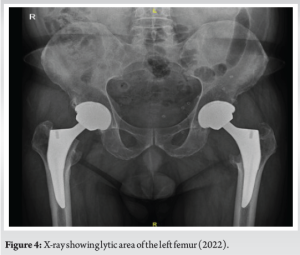

He presented to us in November 2022 with pain in the left hip of 2 months duration without any history of fall. His pain was dull, aching in character, radiating from the left groin to the left thigh. The pain aggravated with weight bearing. His pelvis with both hip X-rays revealed a large amount of periacetabular osteolysis with osteolysis seen around the greater and lesser trochanteric area with complete resorption of calcar (Fig. 4). He had normal erythrocyte sedimentation rate, C-reactive protein, procalcitonin, and metal ion levels (cobalt, chromium). His computed tomography (CT) scan report showed osteolysis around the roof and posterior wall of the acetabulum with peri-implant osteolysis. There was partial resorption of the greater and lesser trochanters and intertrochanteric region with associated large peri-implant soft tissue mass of size 13 × 6 cm (Fig. 5). His positron emission tomography-CT shows low metabolic activity around the peri-implant soft-tissue mass, suggestive of a benign tumor with no metastasis. The case was discussed in the hospital tumor board meeting and planned for ultrasound (USG)-guided fine needle aspiration cytology (FNAC) from soft-tissue mass. FNAC report was suggestive of a blood clot with blood-derived leukocytes, and no atypical cells were seen. Since FNAC was inconclusive patient was planned for a staged procedure, i.e., stage 1- excision of soft tissue mass along with explantation of the prosthesis, and stage 2- revision THA. The patient deferred surgery for 2 weeks, and he reported back to us with increased intensity of pain; hence, the patient was planned for staged surgery.